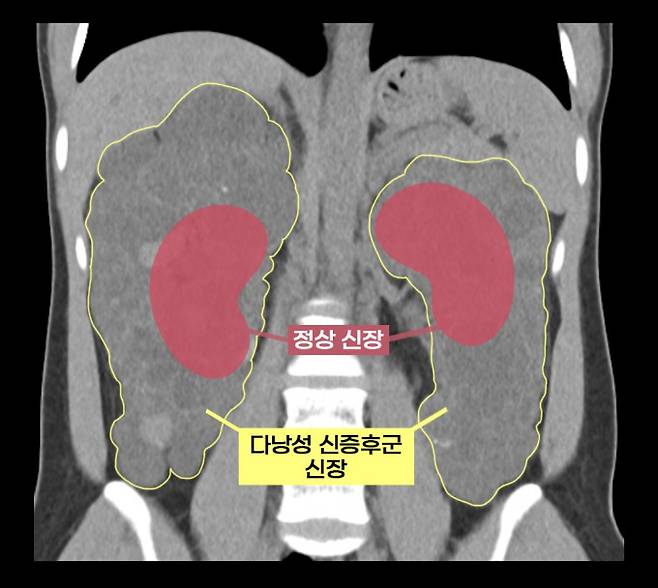

신장에 다수의 낭종이 생기는 질환인 '다낭성 신증후군'으로 신장이 7배 커진 환자가 신장을 제거하고 이식하는 로봇 수술을 받았다.

이 씨는 상염색체 우성 다낭성 신증후군을 앓았다. 신장에 셀 수 없이 많은 낭종이 발생해 신장이 최대 축구공만큼 커지는 유전 질환이다. 1000명 중 한 명꼴로 비교적 흔하게 발생하며 대부분 만성 신부전으로 이어진다.